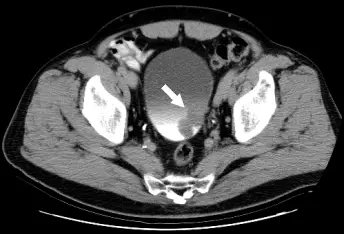

46 歲林先生因排解血尿而到醫院檢查,他並沒有其他不舒適症狀。醫師為他做 IVU 檢查顯示膀胱異常,又進一步做 CT 檢查,病變如圖示。林先生最可能患了什麼病? 圖片 圖片 圖片

圖一(IVU 骨盆 X 光,造影劑充盈期):正面觀骨盆攝影顯示膀胱充滿顯影劑(標示 "FULL"),白色箭頭(×2)指向膀胱左後壁,可見局部充盈缺損(filling defect)——即膀胱輪廓不規則,造影劑無法充填之處,提示有腫塊突入膀胱腔內。此為膀胱腫瘤的典型 IVU 表現。